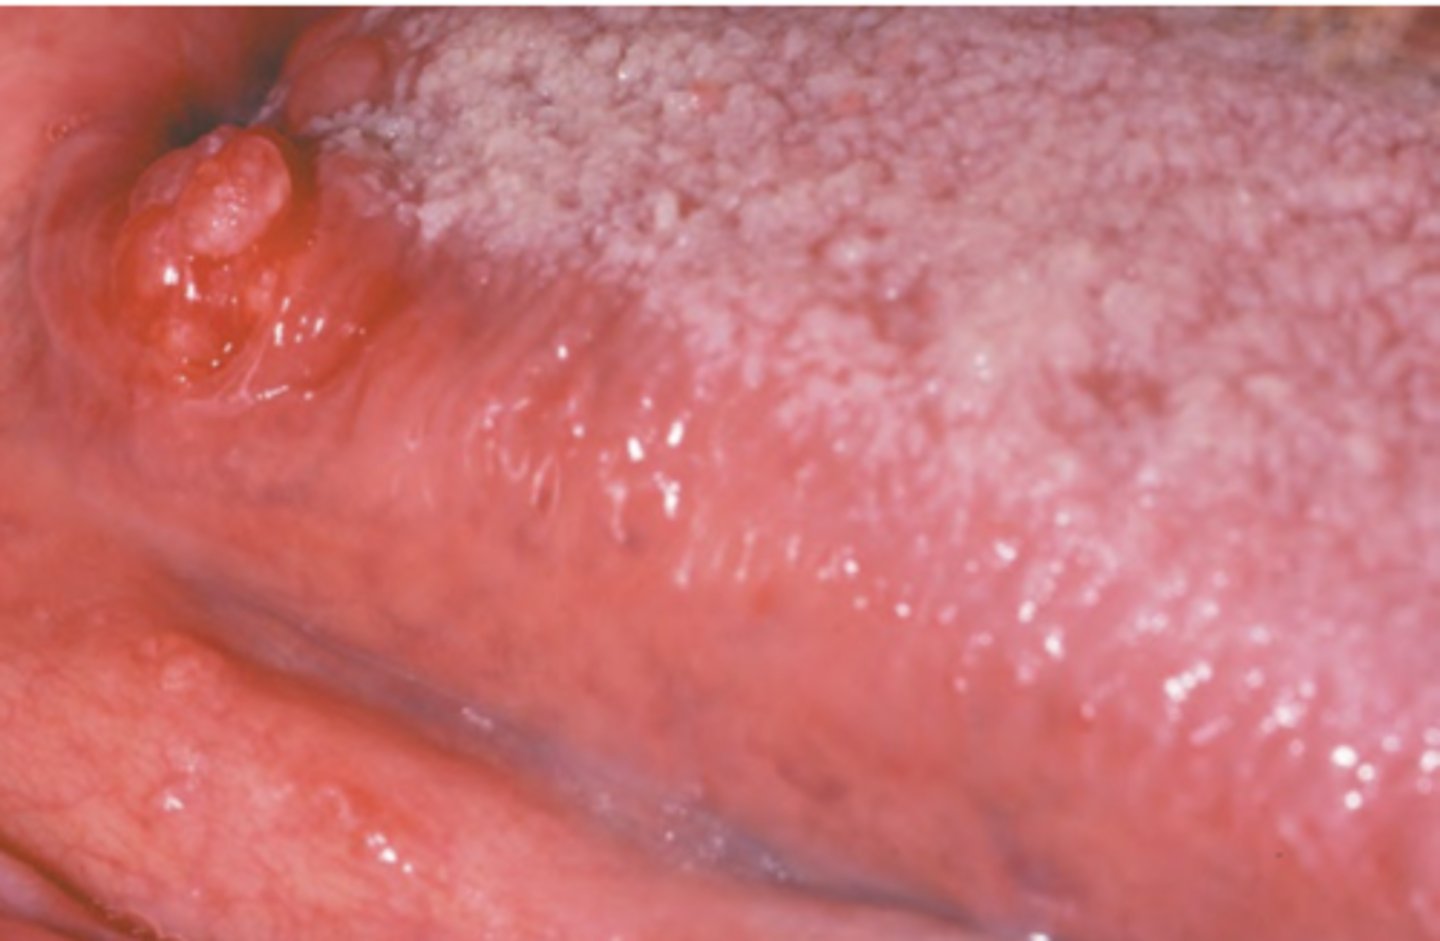

Squamous Cell Carcinoma (intraoral)

Hint: most common sites of this pathology are tongue (posterior lateral and ventral) and floor of mouth

Squamous Cell Carcinoma (floor of mouth)

Diffuse erythematous speckled plaque on floor of mouth; most likely to arise from existing leukoplakia